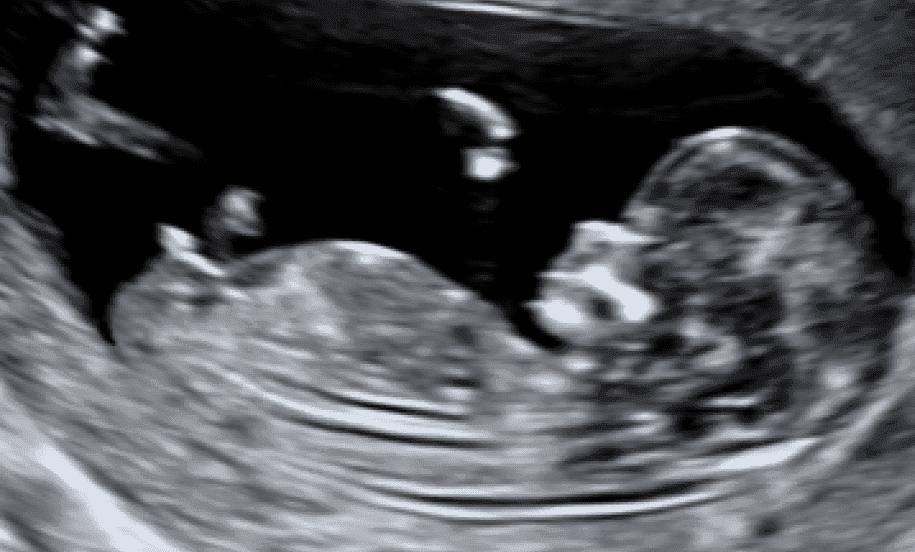

Dating Scan

- Patvirtinkite, kad ankstyvas / perspektyvus nėštumas yra vienas ar keli

- Nustatykite vaisiaus nėštumo amžių.

- Nuo 8 iki 14 savaičių.

- Karūnos ilgio (CRL) matavimas.

- Širdies plakimo patvirtinimas

- 2x b / w vaizdai.

- 30 min susitikimas.